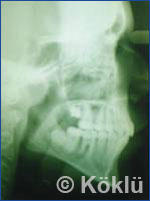

Röntgenbild vor- und nach einer Behandlung mit dem Biofunktionell Protrusive Snap-System

Der erste Schritt ist eine muskuläre Anpassung des Körpers auf die, durch die Funktions-Kieferorthopädischen Geräte vorgegebene, neue Position der Kiefer zueinander. Der zweite Schritt ist eine Anpassung des Kieferwachstums. Auf den nachfolgenden Röntgenbildern eines weiteren Behandlungsfalles wird dies besonders deutlich.